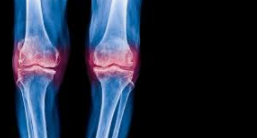

무릎 물참 증상은 말 그대로 무릎에 물이 차는 것으로 무릎관절에 염증이 발생하여 몸에서 염증을 치료하기 위해 관절액이 나오는데 관절액이 고인 증상을 무릎 물참 증상이라고 합니다.

무릎 물참 원인은 앞서 이야기 했듯이 무릎에 염증이 생겼기 때문인데, 무릎 주위 근육 및 인대에 손상이 발생되어 나타나는것이 대부분 입니다. 이러한 경우에는 간단하게 손으로 눌러 어느 위치에 염증이 났는지 쉽게 알 수 있습니다.